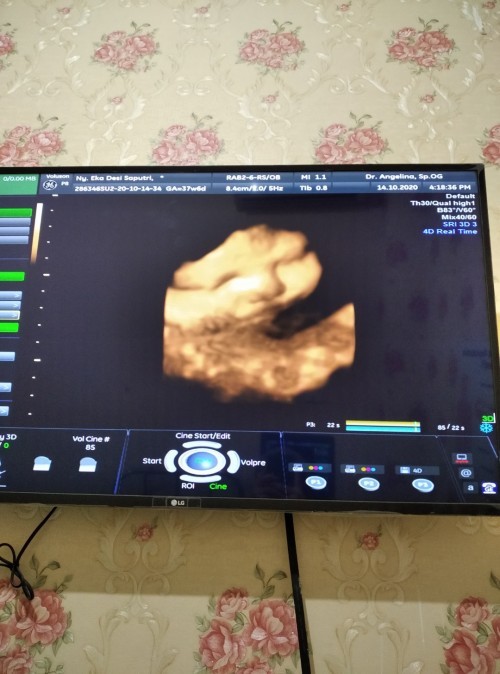

33week tiap usg cemberut mlulu kek ibunya🙊 sekarang udh 38week